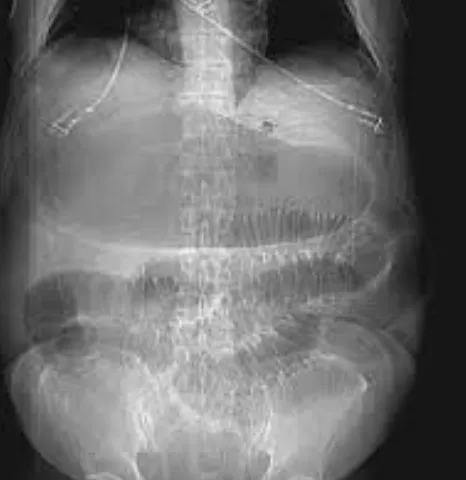

其中有一起事故的受害者为叫米丽莎(Melissa Zoglie),去年4月份因为突然的肚子痛、全身冒冷汗,被送到这个医院,结果医生给她做了一个胸部X光检查,诊断为胃溃疡,开了点药就把她打发回家了。

但米丽莎得的其实是胃扭转,这是一种少见的病症,指胃的大小弯位置发生全部或部分变换,引起上腹剧烈疼痛,急性胃扭转需要手术治疗,而且越拖越严重。

这个病例当时被医院内部调查了,大家发现其实第一天送来医院接受的X光结果显示,那时米丽莎的胃部异常肿大,只是医生见她还很年轻,觉得是重病的可能性小,掉以轻心误诊了。